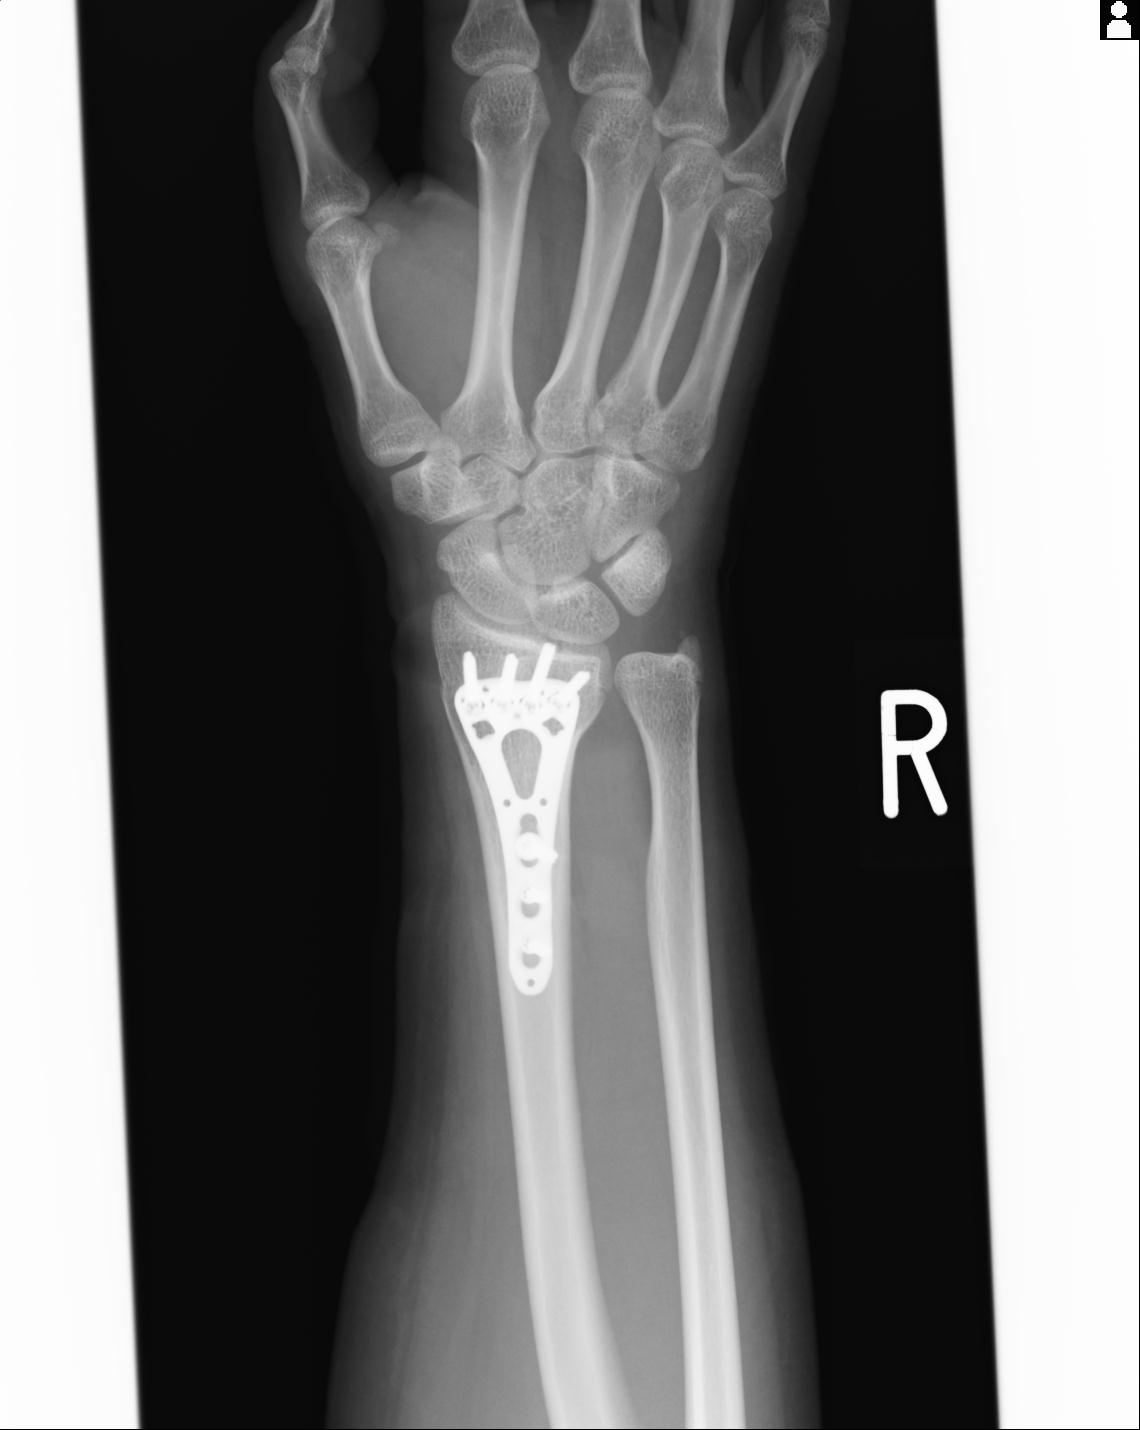

46666 1/23 両股正面+軸と右手関節 2R 76歳女性 右橈骨遠位端